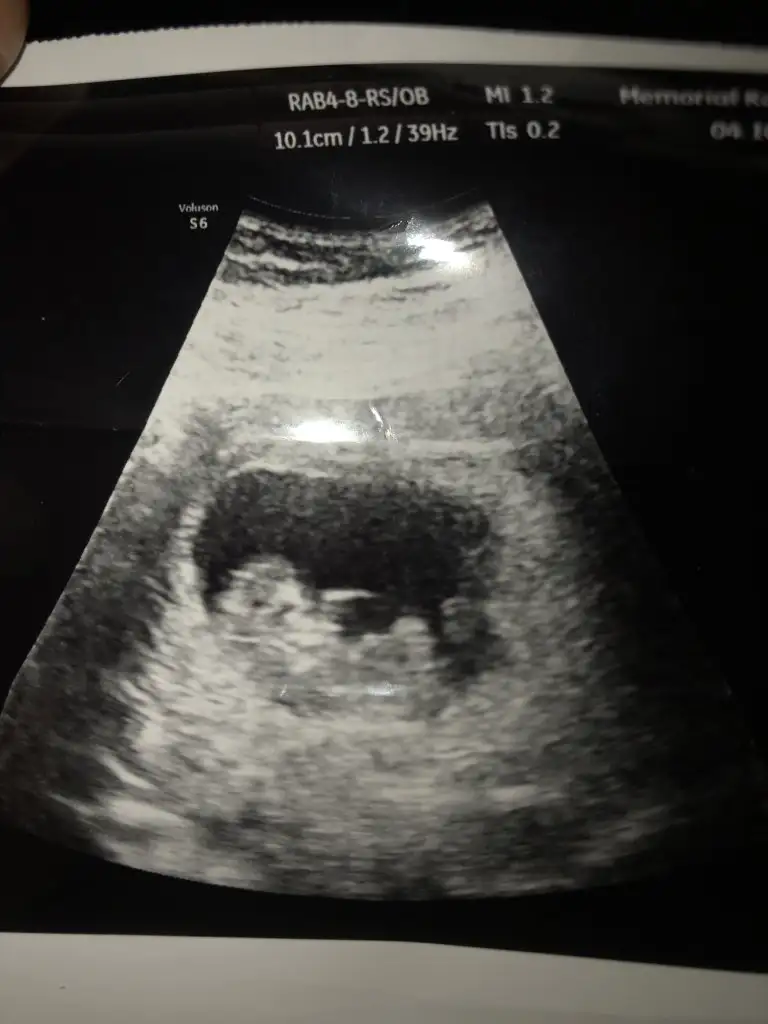

Merhaba kizlr. Devlte gittim anca bu kdarlik gorntu var. Sizce neye benzio. Tam 11 haftlik